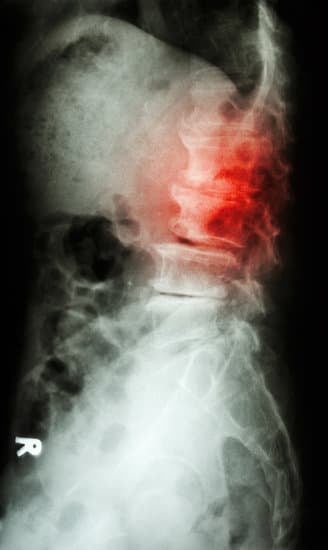

X-선 검사

X-선 검사는 척추의 뼈 구조를 평가하여 전위증의 존재 및 정도를 확인하는 데 사용됩니다.

X-선은 뼈가 얼마나 이동했는지, 주변 뼈에 어떤 영향을 미쳤는지 볼 수 있도록 해 줍니다.

때로는 환자에게 서 있을 때와 앉아 있을 때의 X-선을 찍어서 척추의 변화를 비교하기도 합니다.